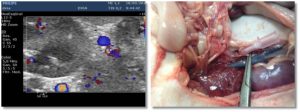

Esta es una sección realizada en colaboración de los compañeros veterinarios con los que trabaja DXIA, en la cual, compararemos imágenes reales, obtenidas durante la resolución quirúrgica, con imágenes ecográficas.

Una forma que puede ser interesante de colaboración y que nos ayuda a poder darle color a las imágenes obtenidas durante un estudio ecográfico seria comparar las imágenes reales que se obtienen durante las cirugías o intervenciones con las imágenes diagnósticas obtenidas durante el estudio ecográfico del paciente. Os quiero animar a todos a que mandéis dichas imágenes y a que este apartado crezca día a día.